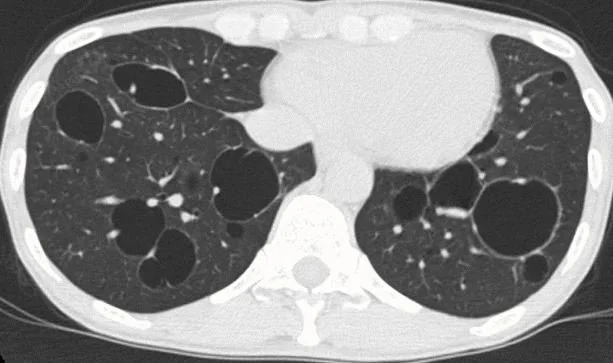

Our patient had lymphangioleiomyomatosis (LAM).  This is a rare cystic lung disease that occurs mainly in young women in childbearing years.  It is rare,  but 50% of patients present with pneumothorax  resulting in presentations for emergency care. It is often found in association with tuberous sclerosis complex(TSC) and is a congenital defect associated with TSC1 and TSC2 gene mutations. These mutations lead to dysregulation of the rapamycin (mTOR) signaling pathway resulting in unchecked muscle cell growth in the lung.  This leads to air trapping, creating thin-walled cysts that can rupture.

thin walled cysts in LAM